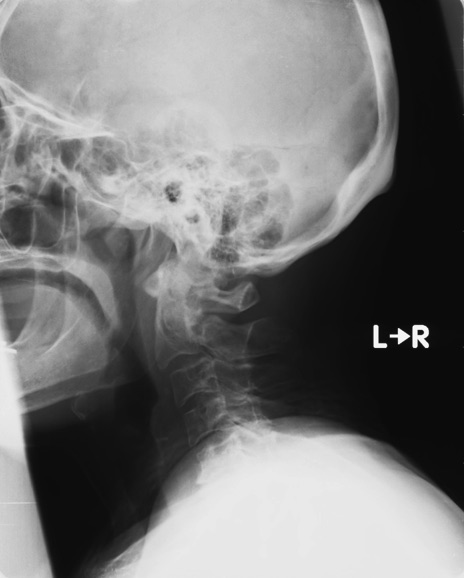

症例48 頚椎レントゲン(側面像)

【症例】80歳代女性

【主訴】頸部痛

【現病歴】昨日家の階段を2段くらい上がったところで転倒して受傷。

異常所見と診断は?

頚椎レントゲン